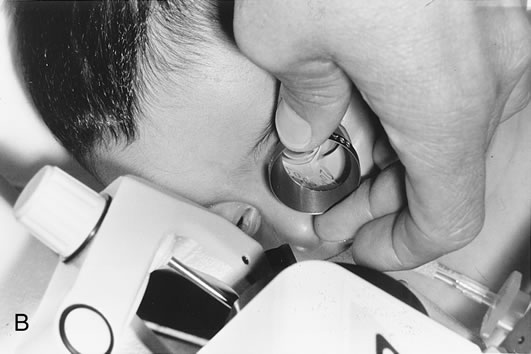

When phacoemulsification became available, it was quickly applied to the removal of children's cataracts because it provided the surgeon with better control of the flow of irrigating solutions and provided improved control of the aspiration flow and pressure.4 The instrument also added a new capability, that of being able to mechanically disrupt the lens nucleus and cortex to facilitate aspiration of the lens. Although the phacoemulsification instrument was helpful for removing lens cortex, it was ineffective in cutting or removing the posterior lens capsule. At the conclusion of the phacoemulsification procedure, the posterior capsule was left intact. When capsular opacification occurred, it was treated with a discission procedure, an operation that consisted of making a cut in the posterior capsule with a bent needle, a Ziegler knife, or a modification of the latter (Fig. 1). If the membrane was thick and resisted opening with a knife, an intraocular scissors was necessary to open the lens capsule.

The advantage of leaving the posterior capsule of the lens intact after cataract surgery is that it retains a barrier between the anterior chamber and vitreous. This prevents the vitreous from entering the anterior chamber, and it theoretically preserves the ocular anatomic relationships after cataract surgery. The disadvantage of leaving the posterior lens capsule intact is that when the capsule opacifies, a second procedure is needed to re-establish a clear visual axis. To achieve this, a second anesthetic is administered and an incision is made into the clear cornea. The chamber is deepened with a viscoelastic material and a knife or other instruments are introduced into the anterior chamber to cut or tear the posterior capsule so that the visual axis can be cleared (Fig. 1).

The Nd:YAG laser provides the ophthalmologist with the ability to open the posterior lens capsule without making a surgical incision. Because of this, the risk of infection and of complications related to making the incision and introducing instruments into the vitreous are reduced. In older cooperative children, the procedure can be performed in an office setting (Fig. 3).

Until recently, application of laser technology for young or uncooperative children has been difficult because the instrumentation is bulky and difficult to transport. To some extent, these problems have been reduced with a reduction in the size of the laser. Use of the Nd:YAG laser to open the posterior lens capsule in young children has required that the patient be treated in a seated position. If the child is young or uncooperative, some surgeons have resorted to anesthetizing the child near the location of the Nd:YAG laser and have performed the laser treatment on the child while he or she is held in position for use of the laser delivery device. With this technique, there can be problems with positioning the eye, and if the child is treated at a location that is remote from the operating room, there may be difficulty in monitoring the child's anesthetic and providing emergency treatment if this would be required.

To overcome these difficulties, the Nd:YAG laser has been modified so that a posterior capsulotomy can be performed on a child in the supine position. The laser delivery systems now provide the surgeon with the ability to safely perform an Nd:YAG laser capsulotomy in children in the operating room with the assistance of sedation or, if necessary, general anesthesia (Fig. 4). In 1994, Atkinson and Hiles demonstrated the effectiveness of the Nd:YAG laser in children 3 months of age and older.29 The surgeon may elect to perform the Nd:YAG capsulotomy immediately after cataract surgery or at a later date, when the capsule has become tense or has begun to opacify.